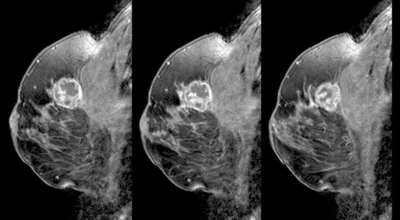

개인마다 초기증상은 다르게 나타날 수 있어요. 유방암은 우리나라 여성암 1위인만큼 많은 여성분들이 유방암에 대해 관심이 많아 검사를 많이 하는 추세입니다. 스트레스를 많이 받는 젊은 여성들도 유방 통증으로 진단을 받는 경우가 늘고 있다고 해요. 경우에 따라서는 유방암 초기증상이 없을 수도 있답니다. 유방암 자가검진 후 증상이 발견된다면 빨리 병원에 방문하는 편이 좋아요.

2. 유방암 초기증상 - 유방의 혹

보통 응어리가 잡히는 분들의 40%는 물혹으로 가벼운 질병으로 바로 치유가 되는 경우가 많은데요 20~30%의 확률로 유방암 초기증상일 가능성이 있다고 하죠. 따라서 매일같이 자신의 가슴을 마사지 해주시다 어느 날 응어리가 잡히게 된다면 유방암 검사 초기에 받아 보시기를 권해 드립니다.